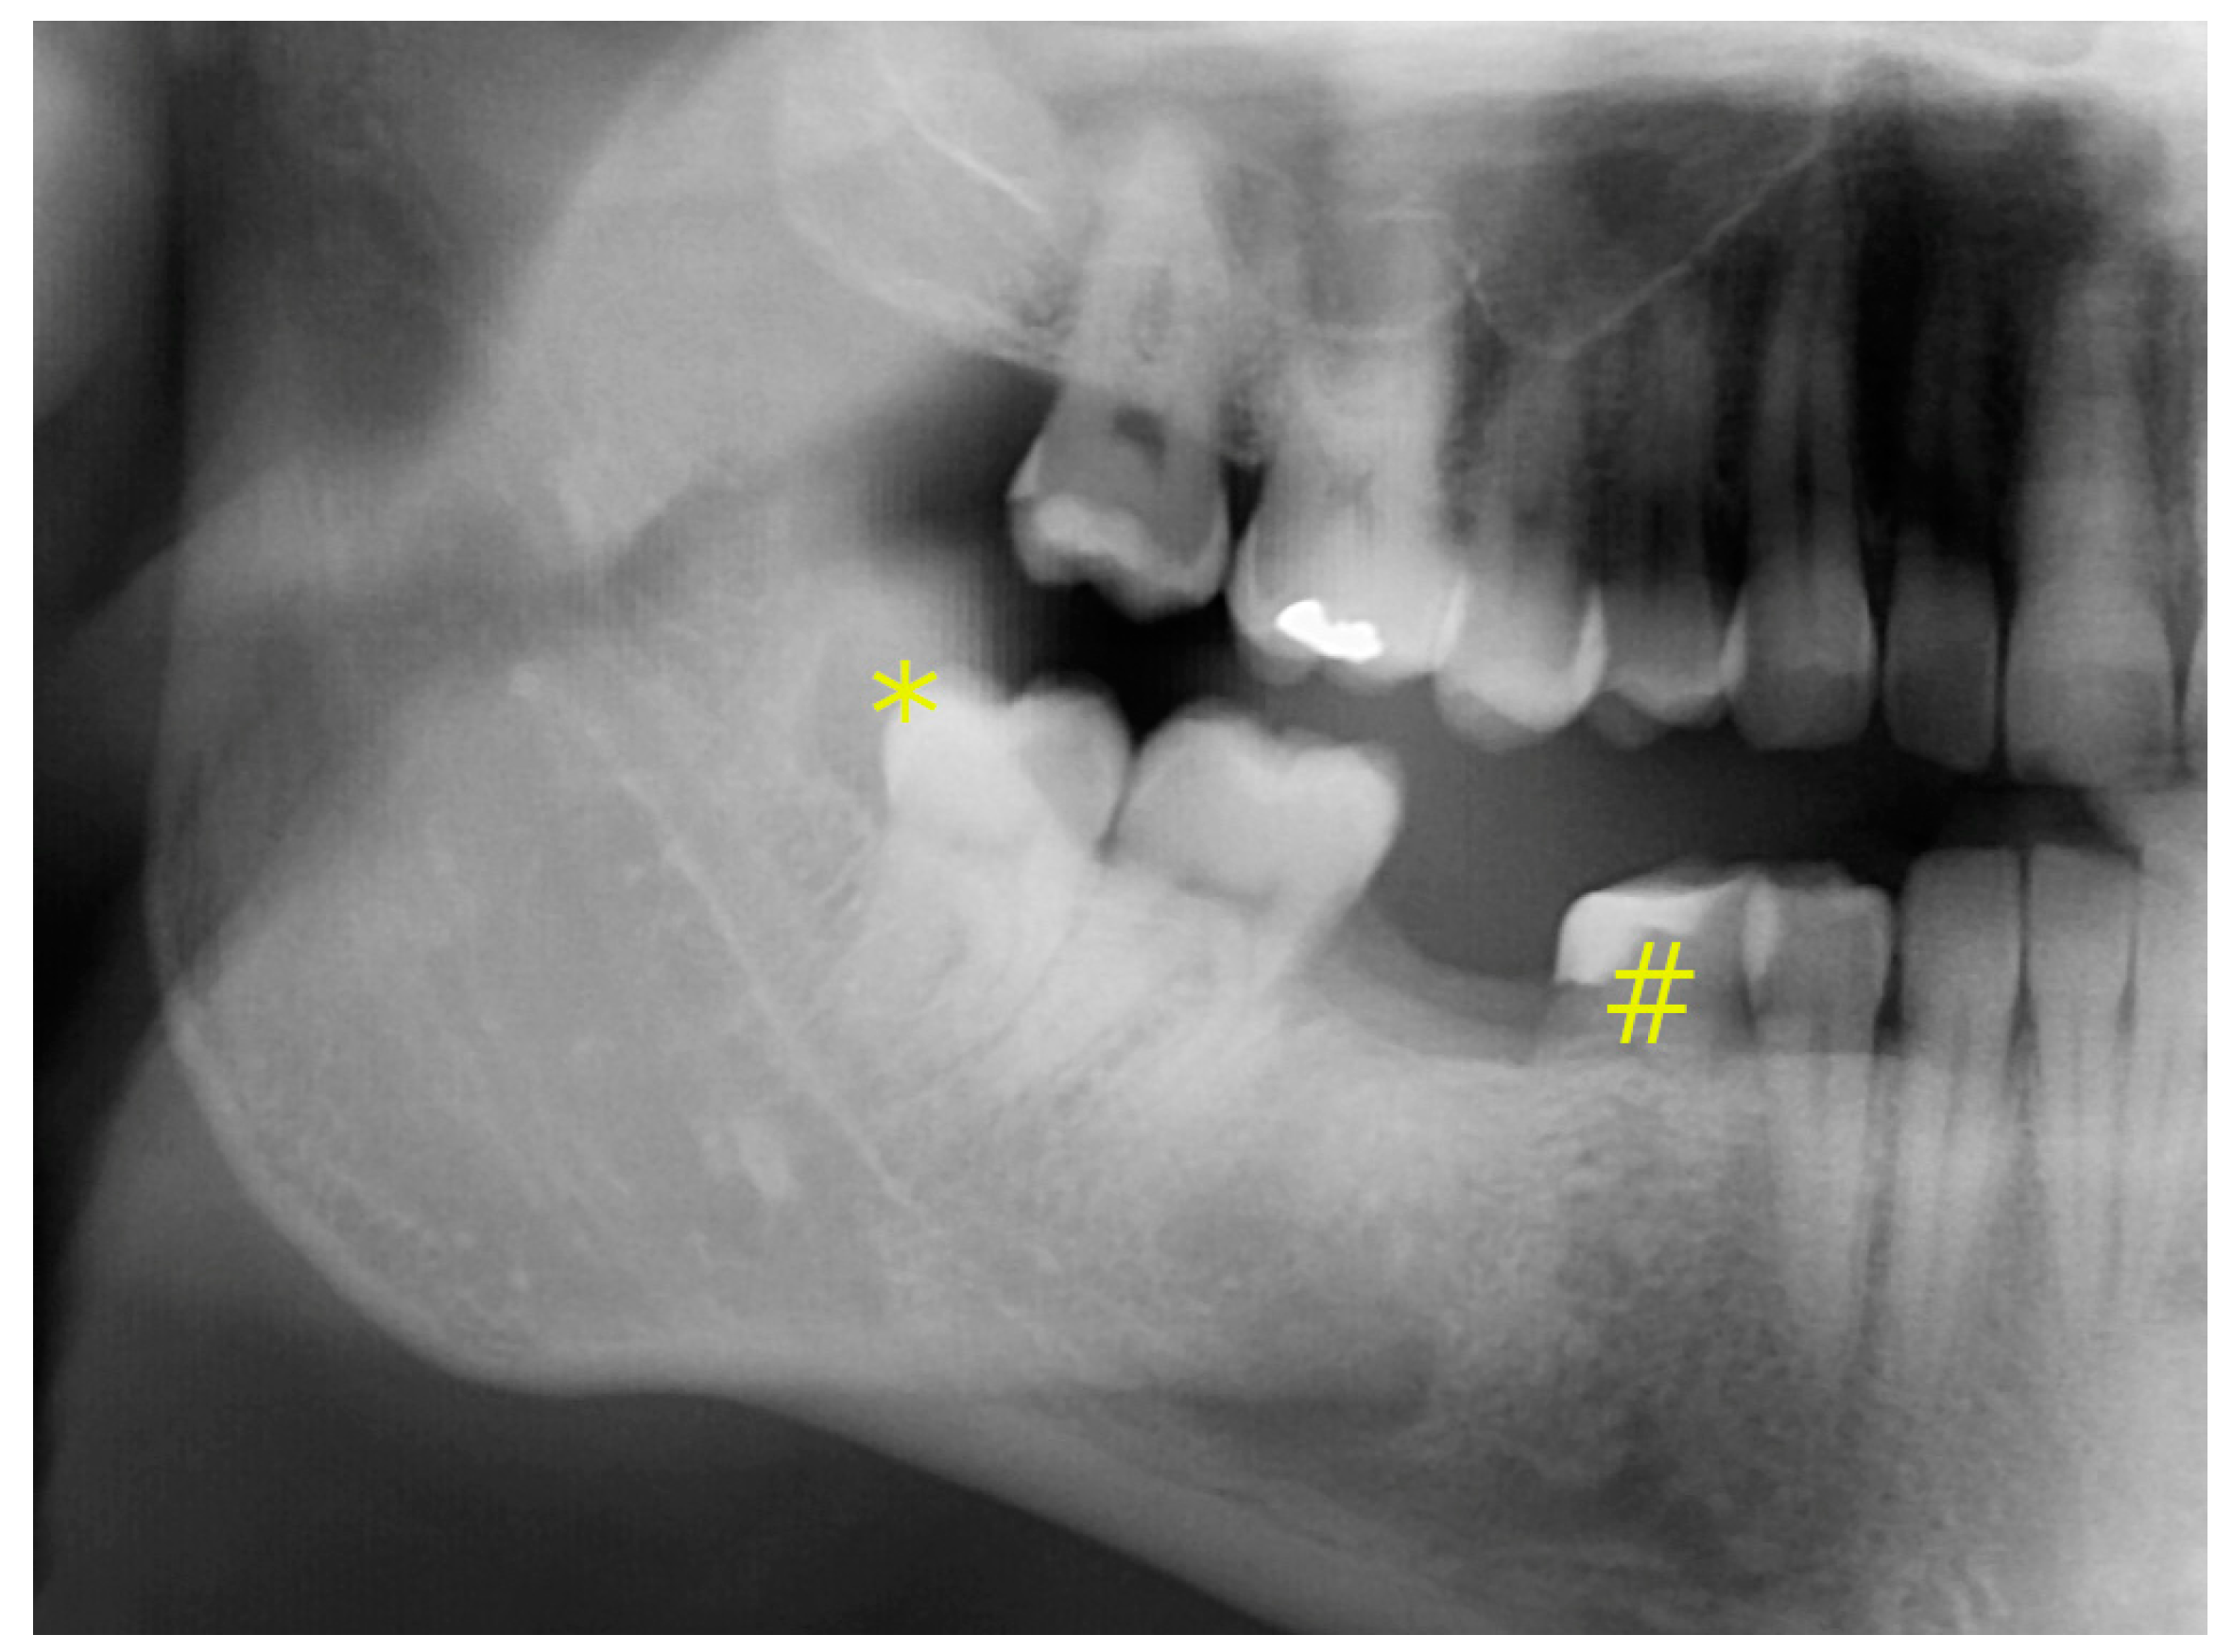

2. Report